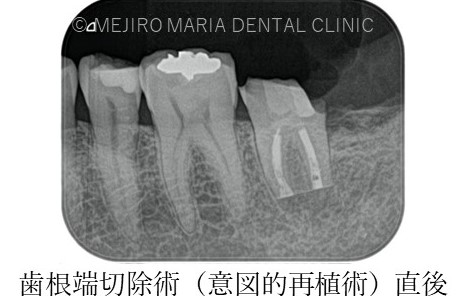

その場合、もう一度根管治療を行っても根管内の細菌を無菌化できるわけではなく、更に歯質を大きく削ることになるため、外科的歯内療法(歯根端切除術)にて問題を解決します。

今回のような最後方臼歯(一番後ろの歯)に対しては、解剖学的に骨の厚みや器具の到達を考え、意図的再植術を適応させることになります。

違和感や痛みは術後1ヶ月程で消失し、3ヶ月後には術直後に見られていた左下7番根尖部に確認できた透過像も消失し、順調に骨が作られていることが確認できます。